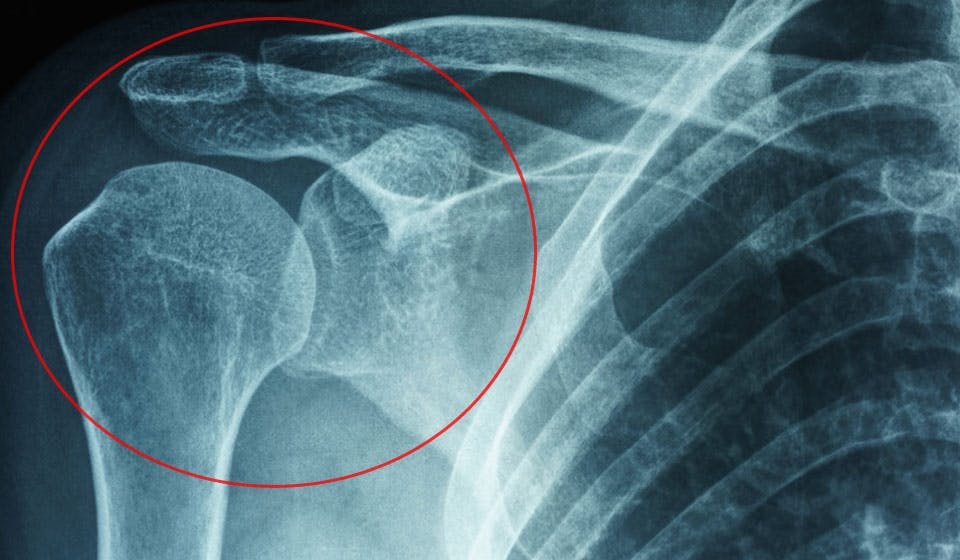

I skulderen er overarmsknoglen fæstnet til skulderbladet i et led, der holdes på plads af en bindevævsfyldt kapsel. Ved en frossen skulder opstår der en slags betændelse i ledkapslen. Det gør bindevævet stift. Samtidigt vokser der unormalt væv frem, og produktionen af smørende ledvæske hæmmes. Det går drastisk ud over din bevægelsesevne og giver dig smerter.

FROSSEN SKULDER I skulderen sidder overarmsknoglen fast til skulderbladet i et led, der holdes på plads af ledkapslen, som fastholdes af bindevæv. Frossen skulder skyldes, at der opstår betændelse i ledkapslen, og det medfører at bindingsvævet bliver strammere og stivere.